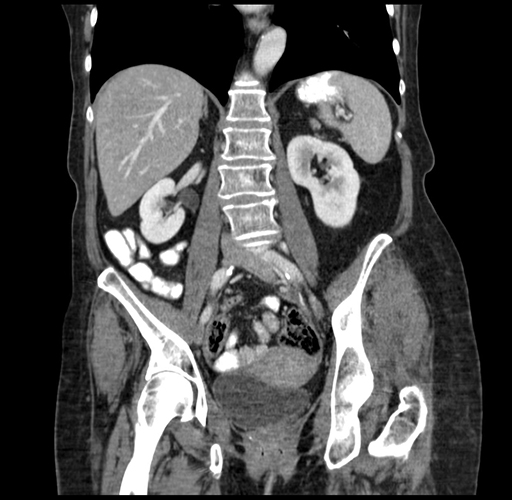

Coronal Venous